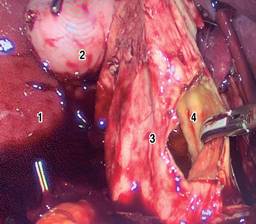

Se programó una resección electiva por vía laparoscópica (Figura 5) tras completar un protocolo preoperatorio exhaustivo. Los hallazgos intraoperatorios evidenciaron el QC-IVA-Todani-modificada, con una vesícula biliar atrófica. Se inició la disección de la cápsula del quiste intentando separarla de las estructuras vasculares (vena porta y arteria hepática). Se decidió abrir el quiste para facilitar su disección, pero debido a su fuerte adherencia y vascularización, con un sangrado escaso pero continuo, se convirtió en una cirugía abierta mediante una incisión tipo Kocher.

Figura 5: Laparoscopia. Apertura del quiste de colédoco en su pared anterior; (1) lóbulo derecho hepático, (2) vesícula biliar, (3) serosa pared anterior del quiste, (4) mucosa pared posterior del quiste.

Se continuó la disección del quiste separándolo de la vena porta sin dañarla. A través de la apertura del quiste, se introdujo un dilatador de Bakes para identificar y canalizar los conductos hepáticos derecho e izquierdo dilatados. Luego se realizó la extirpación del quiste de colédoco desde la bifurcación de ambos conductos intrahepáticos hasta el borde duodenal, donde se practicó una sutura continua con polidioxanona incluyendo el último centímetro del conducto colédoco, realizando así una extirpación completa del quiste, incluyendo la vesícula biliar. Para finalizar, se realizó una derivación biliodigestiva en Y de Roux, con un asa yeyunal a 50 cm del Treitz, y un asa para el drenaje biliar de 50 cm, utilizando una engrapadora lineal de 60 mm en la hepático-yeyuno anastomosis.